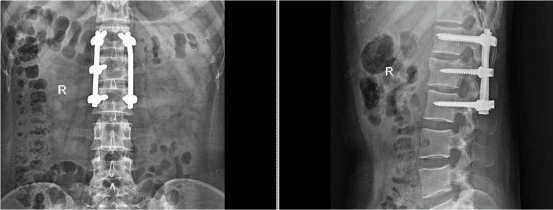

2. 手术治疗

①严重压缩性骨折及出现并发神经症状者,选择切开复位内固定治疗。

图片